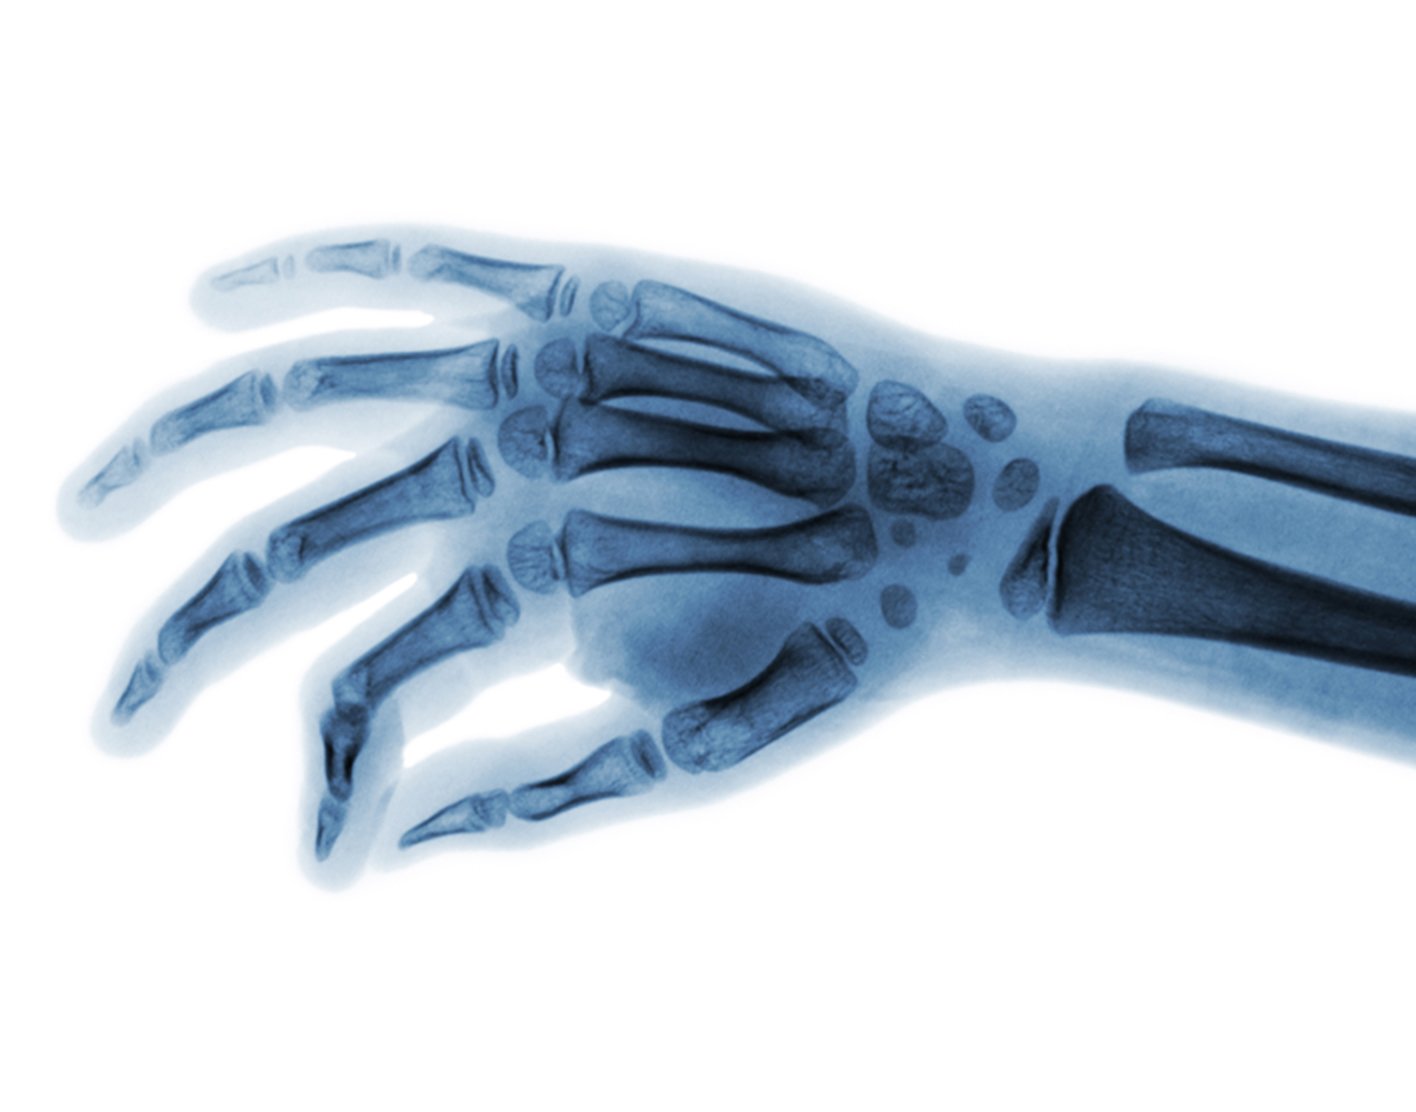

Joint x-ray

This test is an x-ray of a knee, shoulder, hip, wrist, ankle, or other joint.

X-ray - joint; Arthrography; Arthrogram